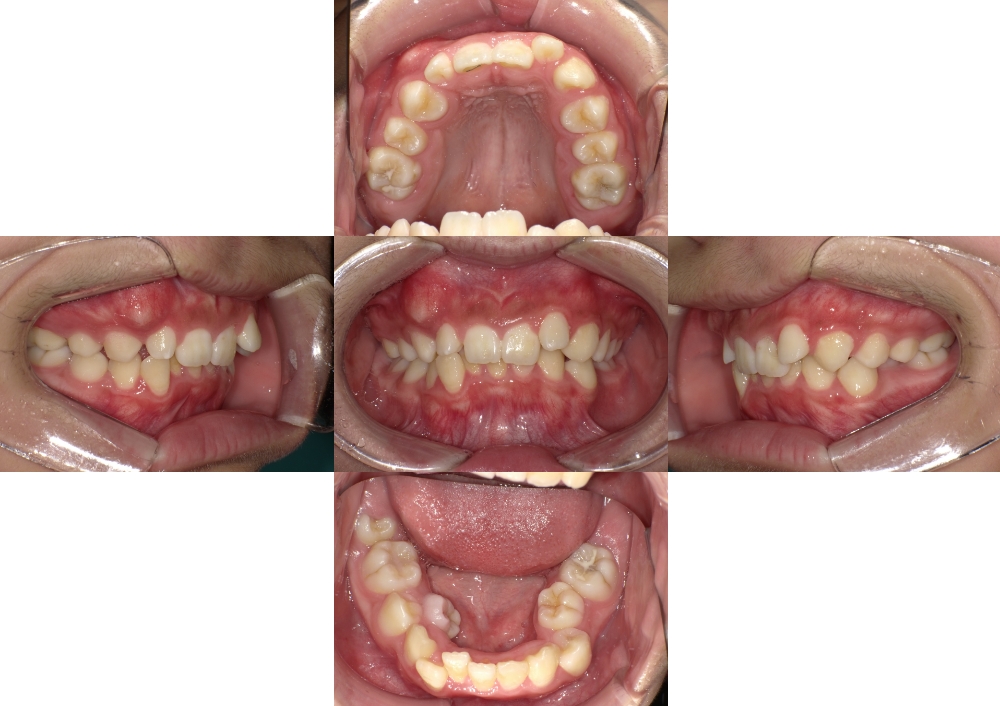

症例2

叢生

抜歯

ブラケット矯正

(初診時)年齢

13歳

性別

男性

地域(住所)

府中市

主訴

デコボコ

診断

右上3番の埋伏歯および下顎両側5番の先天欠損を伴う叢生

装置

カリエールエモーション、マルチブラケット装置

抜歯/非抜歯

下顎両側E抜歯

期間

2年9か月

費用

730,000円(税抜)(矯正装置・保定装置代込)

調整料 5,000円 (税抜)× 33回

症例写真

BEFORE